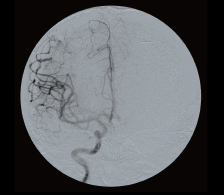

Увеличение, контраст, реверс, поворот, наложение фильтров, контуров и многое другое. - Программный пакет для цифровой субтракционной ангиографии

Позволяет проводить интервенционные вмешательства на сосудах. Включает следующие режимы: виртуальная коллимация, Road MAP, Re-Mask, MAX OP.